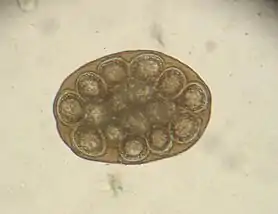

(photo prise au microscope)

Dipylidium est un genre de vers plats de la famille des Dipylidiidae selon World Register of Marine Species (31 octobre 2023)[1], dont les espèces sont responsables de tæniasis chez l'humain. Le genre Dipylidium caninum, répandu partout sur le globe, est le ver solitaire le plus fréquent chez le chien. Il affecte aussi occasionnellement les chats. Les vecteurs sont la puce, les acariens (Trichodectidae) et pour le chat le pou du chat domestique. Les œufs du ver Dipylidium se détachent du corps des larves et se développent jusqu'à atteindre eux-mêmes le stade larvaire de cysticercoïde. Ces larves s'introduisent dans l’intestin du chien lorsque le mammifère ingère des puces, et elles atteignent le stade adulte en l'espace de 20 jours. Leur taille est alors de 10–70 cm de longueur et de 2–3 mm de largeur. Il contamine le milieu par transmission des puces à d'autres chiens ou chats.